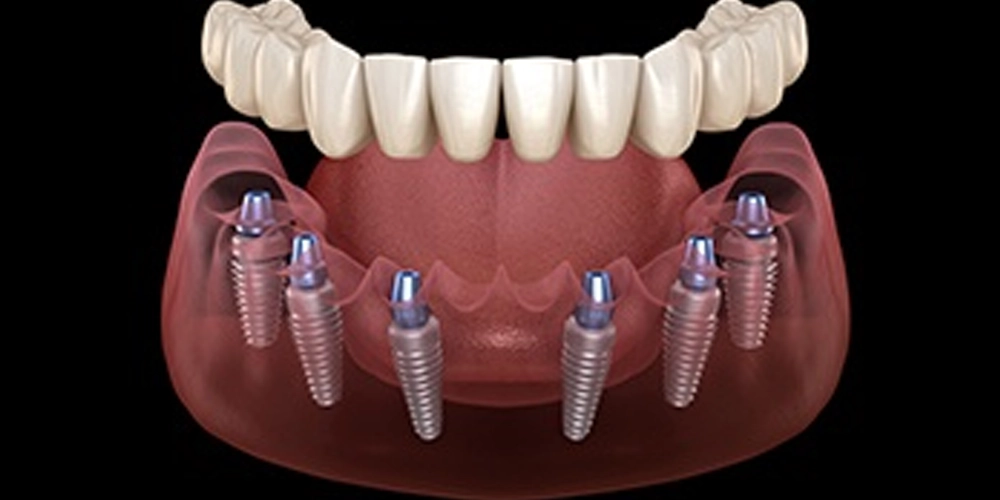

Les implants dentaires sont des vis en titane qui servent de racines artificielles. Placés chirurgicalement dans l’os de la mâchoire, ils fusionnent avec l’os pour fournir une base solide aux prothèses dentaires comme les couronnes, les ponts ou les dentiers. Cette solution permanente restaure efficacement la fonction et l’esthétique des dents manquantes, améliorant la mastication, la parole et la confiance globale d’une personne.

Implants dentaires à l’Hôpital Universitaire Atlas : une solution permanente pour les dents manquantes

À l’Hôpital Universitaire Atlas, nous sommes spécialisés dans les implants dentaires, offrant une solution durable et d’apparence naturelle pour la perte de dents. Nos chirurgiens buccaux et dentistes experts réalisent cette procédure précise pour remplacer les dents manquantes, créant une base stable et permanente pour votre nouveau sourire. En choisissant les implants dentaires à l’Hôpital Universitaire Atlas, vous investissez dans une solution à long terme qui restaure votre capacité à mâcher, à parler et à sourire avec confiance.

La procédure d’implant dentaire à l’Hôpital Universitaire Atlas

La procédure d’implant dentaire à l’Hôpital Universitaire Atlas est un processus soigneusement planifié.

- Procédure : Pose d’implant dentaire.

- Durée : Dure généralement de 30 minutes à 2 heures.

- Anesthésie : Une anesthésie locale est utilisée pour votre confort.

- Lieu : Toutes les procédures sont réalisées dans les installations dentaires modernes de l’Hôpital Universitaire Atlas à Istanbul.

- Récupération : L’implant a besoin de 3 à 6 mois pour fusionner avec l’os. Une prothèse temporaire peut être utilisée pendant cette période.